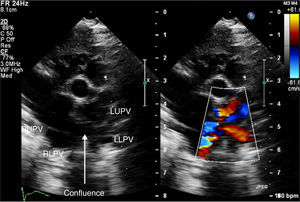

Echocardiography confirmed situs solitus and levocardia. All four pulmonary veins were imaged forming a confluence which opened directly into the right atrium with a mean gradient of 8 mmHg (Figures 1–3). There was no vertical vein and the coronary sinus was normal. Individual pulmonary veins were adequately sized. The ASD was of ostium secundum type, measuring 4.7 mm, with mildly restrictive peak and mean gradients of 5 and 1 mmHg, respectively. Surgical exploration revealed all pulmonary veins draining to the right atrium with a shelf over the opening of the left pulmonary veins. The patient underwent primary sutureless TAPVC repair and closure of the ASD with a tanned pericardial patch, and is doing well.